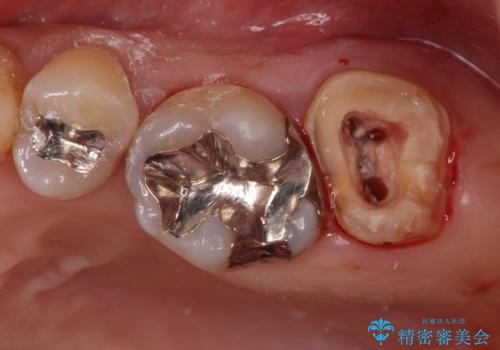

痛みはないとの事でしたがレントゲンを撮影したところ根の先に病巣がある事がわかりました。

被せ物、古い材料を徹底的に除去し、ラバーダム防湿にて無菌的処置を行い、セラミックの被せ物で治療を行いました。

- ジルコニアクラウンスタンダード・仮歯 12.1万円 精密根管治療(リトリートメント) 14.3万円 ファイバーコア 2.2万円費用は治療当時の料金となります